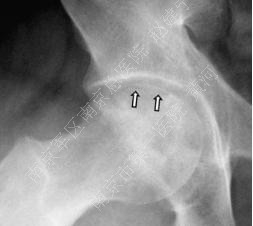

2.影像学检查: 髋部正位片及蛙式位片仍是重要的诊断手段,正位片最初的阳性表现为头下的硬化带及囊性改变,由于正位片中髋臼前后缘与股骨头上方存在重叠,有可能导致病损区显示不清,因此蛙式位片不可或缺,随着病情发展,软骨下骨与软骨分层,X片上则表现为新月征的特点;由于疾病早期X片可无阳性表现,MRI是目前诊断ONFH的“金标准”,其特征性体现在T1加权像上的低密度信号以及T2加权像的高密度信号,是坏死骨与活性骨的交界处出现大量富含血管的肉芽组织的表现。

囊性变及硬化带

新月征

病损周围环绕硬化带(白箭头)软骨下骨折(黑箭头)以及关节间隙狭窄(细长白箭头)

股骨头坏死进展性变化:病损周围硬化带

(白箭头),关节面塌陷,关节间隙严重狭窄,

髋臼软骨下囊肿形成(细箭头)